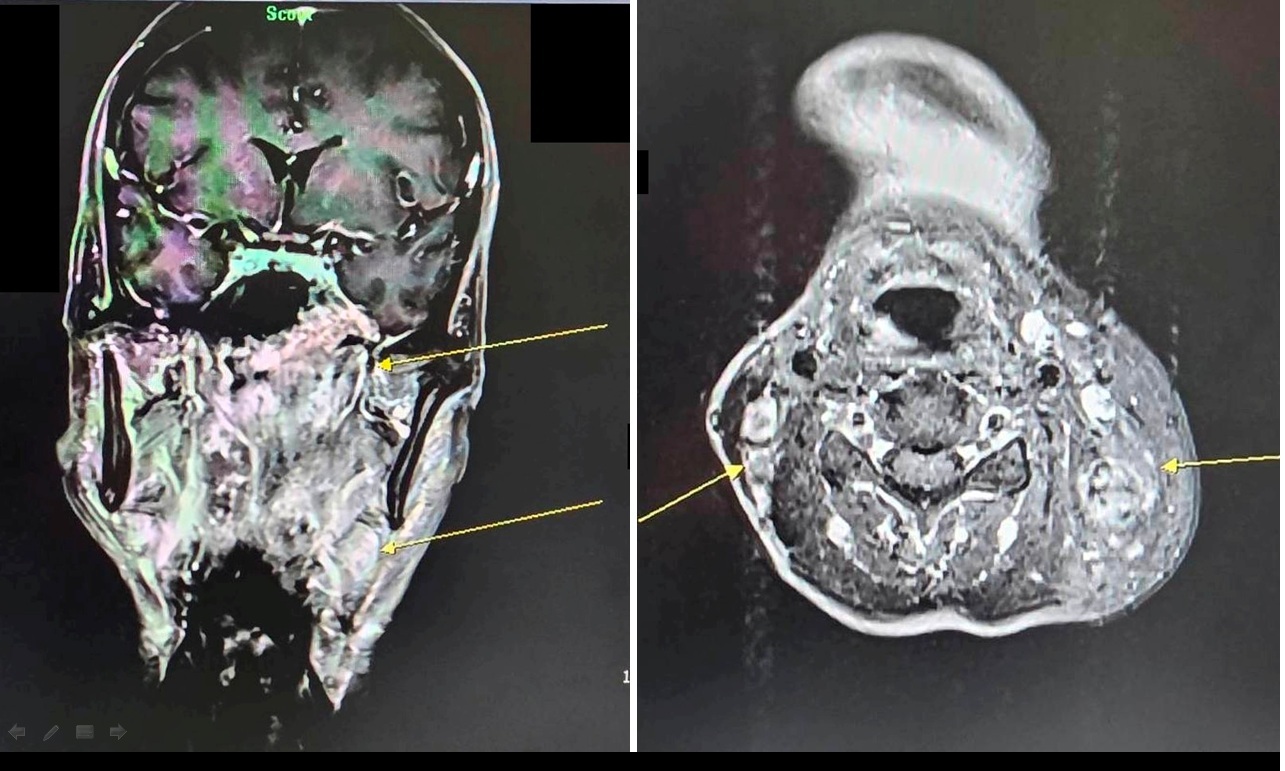

病人透過核磁共振檢查,確診為鼻咽癌(黃色箭頭處)/(照片:大千綜合醫院供)

很多人以為耳鳴只是過勞或耳朵發炎,但這可能是身體發出的癌症警報!50歲的林先生因左耳持續耳鳴且聽力下降,原以為只是單純聽力變差,前往耳鼻喉科檢查。沒想到,經鼻咽內視鏡檢查,竟發現鼻咽部有腫瘤,轉介至大千綜合醫院進一步核磁共振檢查後,確診為鼻咽癌第三期,且癌細胞已轉移至頸部淋巴。所幸,經大千癌症醫療團隊治療後,追蹤至今三年多病情控制良好,無復發或轉移的情形。